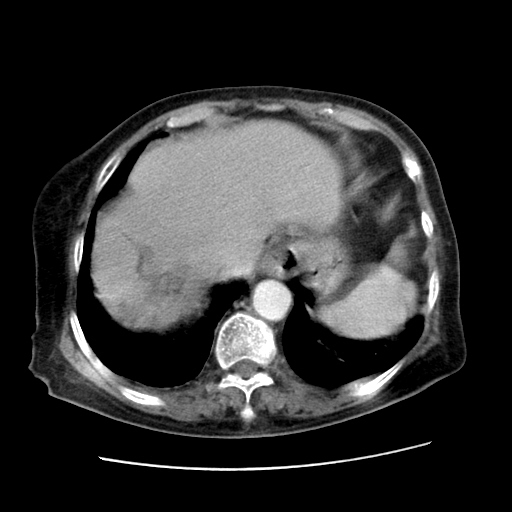

肝脏变异

肝右叶肝内胆管结石并肝内胆管扩张

胆总管扩张

右侧胸腔少量积液(也可能是胸膜增厚不过是什么都一样)

胆囊未见明显显影

肝旁多发胆囊状液体影考虑肠腔积液基中部分囊状景不多外胆囊

肝右叶肝内胆管结石并肝内胆管扩张。胆总管下段梗阻,考虑壶腹部占位。

右侧肝内胆管局限性扩张,其内密度不均匀,扩张的胆管壁增厚,考虑肝内胆管炎合并结石可能性大